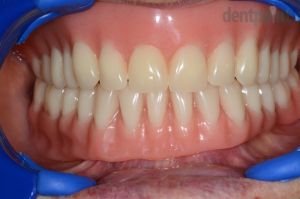

62 éves nő páciensünk előrehaladott fogszuvasodásokkal és csontpusztulással kereste fel rendelőnket. Sajnos ezek miatt egyik foga sem volt megtartható, így implantátumokra rögzített alsó körhíddal, ill. felső kivehető fogsorral pótoltuk hiányzó fogait. A fogeltávolításokat követően 6 héttel történt az implantáció és a csontpótlás. 6 hónap gyógyulást követően készültek el a végleges fogpótlások, azonban a csontosodás ideje alatt az implantátumokat azonnal terheltük, így a páciens rögtön a műtét után ideiglenes fogpótlásokkal távozhatott.

1) Kiindulási helyzet

2) Gyógyult implantátumok

3) Elkészült hídpótlás

4) Esztétikus mosoly